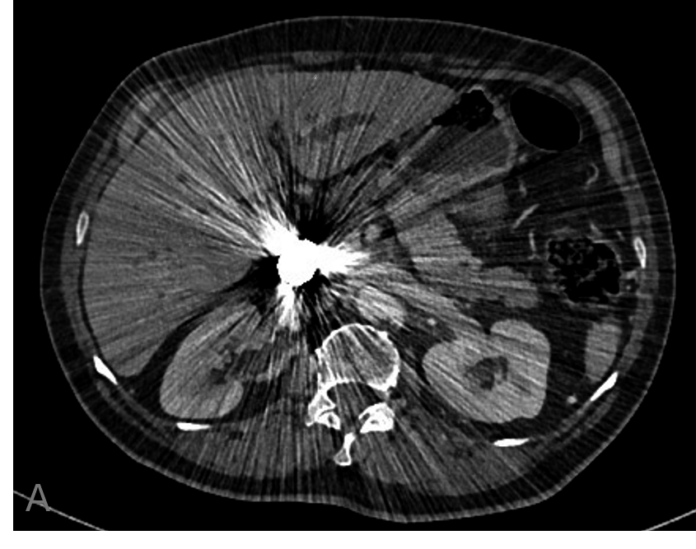

Se le realizaron estudios de imagen de control. En TC de control al año (Fig.6) se visualizan los coils, que no se han modificado, y que condicionan artefacto metálico que dificulta la valoración, el pseudoaneurisma permanece embolizado y la arteria hepática derecha permeable, se observa además progresión de su enfermedad basal, por crecimiento del colangiocarcinoma y dilatación de la vía biliar intrahepática.

En el seguimiento por TC el material metálico de los coils impide la adecuada valoración lo que es un inconveniente para el seguimiento posterior, sin embargo la versatilidad de los coils y su extendida disponibilidad hace que sean un material de embolización muy empleado en caso de emergencias.